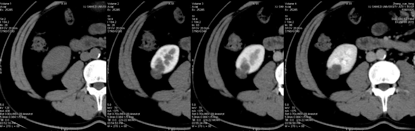

2. 薄层图像三期观察,半数以上医生坚持有强化;初步诊断良性实质性占位。

3. 进行能谱分析,碘含量测量,三期病变内部碘含量相似,且接近0的水平,提示病变没有强化。